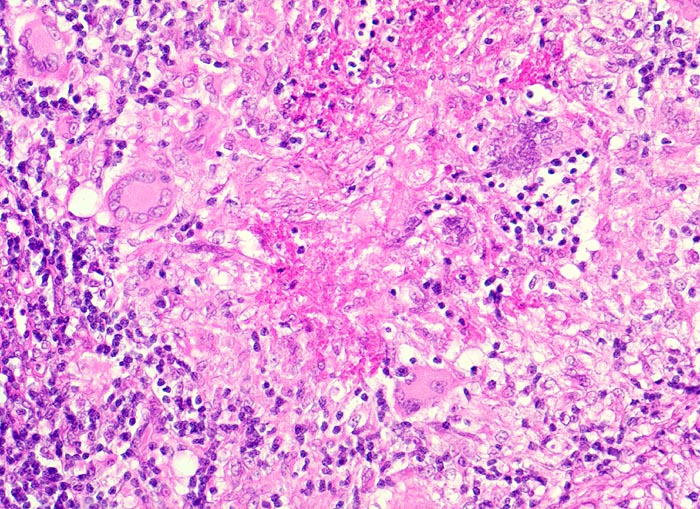

Lymphknotentuberkulose: verkäsendes Granulom

Exsudatives Granulom mit zentraler verkäsender Nekrose. Um die Nekrose gruppieren sich Epitheloidzellen mit reichlich hellem Zytoplasma und Riesenzellen vom Langhans Typ mit hufeisenförmig peripher angeordneten Zellkernen.

Konglomerattumor am Hals mit Fistelbildung bei Patient aus Zimbabwe.